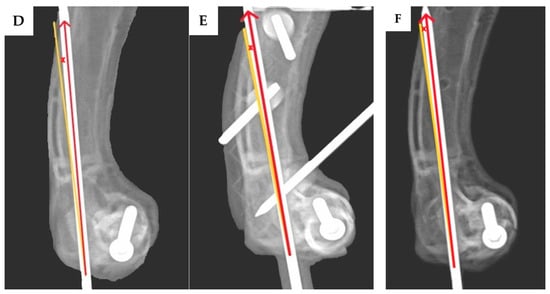

2.4. Assessment of the Transcondylar Screw and Epicondylar Pin Accuracy